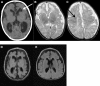

Pyridoxal 5'-phosphate (PLP), the active form of vitamin B6, functions as a cofactor in humans for more than 140 enzymes, many of which are involved in neurotransmitter synthesis and degradation. A deficiency of PLP can present, therefore, as seizures and other symptoms that are treatable with PLP and/or pyridoxine. Deficiency of PLP in the brain can be caused by inborn errors affecting B6 vitamer metabolism or by inactivation of PLP, which can occur when compounds accumulate as a result of inborn errors of other pathways or when small molecules are ingested. Whole-exome sequencing of two children from a consanguineous family with pyridoxine-dependent epilepsy revealed a homozygous nonsense mutation in proline synthetase co-transcribed homolog (bacterial), PROSC, which encodes a PLP-binding protein of hitherto unknown function. Subsequent sequencing of 29 unrelated indivduals with pyridoxine-responsive epilepsy identified four additional children with biallelic PROSC mutations. Pre-treatment cerebrospinal fluid samples showed low PLP concentrations and evidence of reduced activity of PLP-dependent enzymes. However, cultured fibroblasts showed excessive PLP accumulation. An E.coli mutant lacking the PROSC homolog (ΔYggS) is pyridoxine sensitive; complementation with human PROSC restored growth whereas hPROSC encoding p.Leu175Pro, p.Arg241Gln, and p.Ser78Ter did not. PLP, a highly reactive aldehyde, poses a problem for cells, which is how to supply enough PLP for apoenzymes while maintaining free PLP concentrations low enough to avoid unwanted reactions with other important cellular nucleophiles. Although the mechanism involved is not fully understood, our studies suggest that PROSC is involved in intracellular homeostatic regulation of PLP, supplying this cofactor to apoenzymes while minimizing any toxic side reactions.